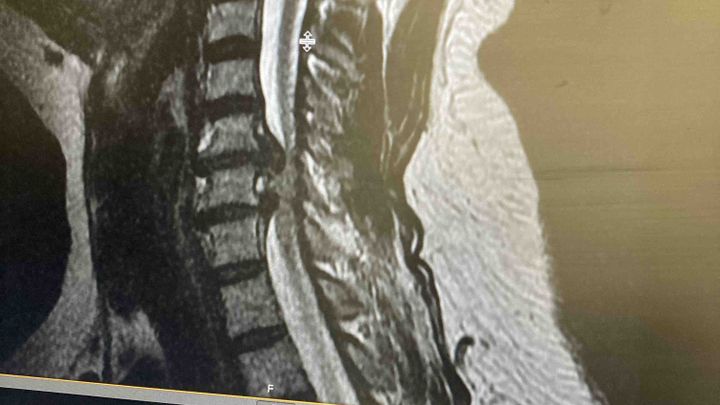

Nicole loves to serve, serve God’s people, serve our community, serve when and where she can! Nicole is currently in a hospital for an emergency surgery on her spine. She pays her bills by working everyday and she will not be working for a little while due to a medical emergency!